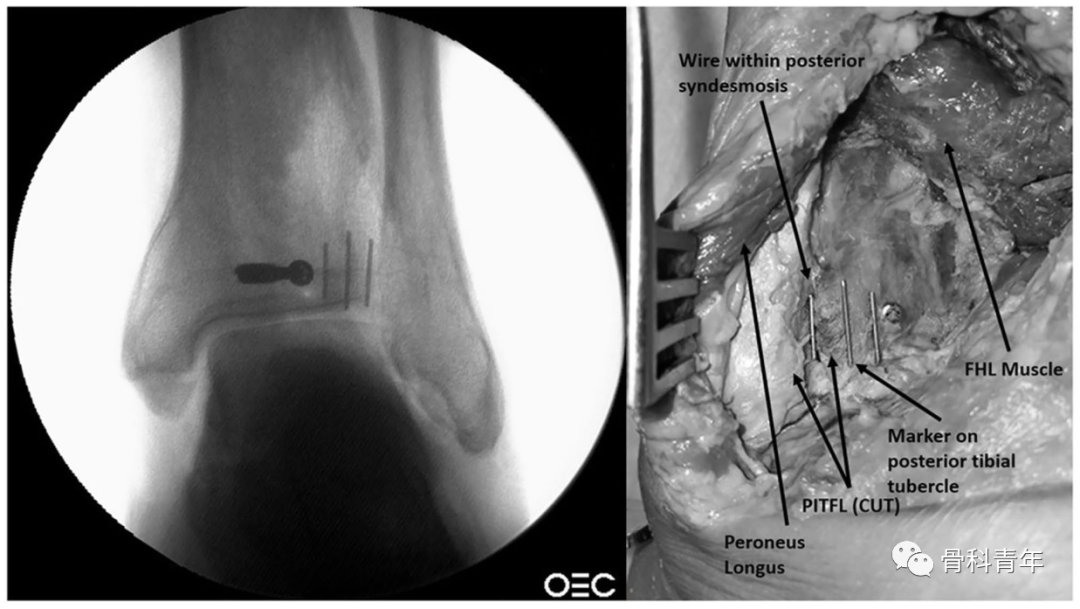

后向前螺钉的置入存在置入下胫腓间隙、激惹踇长屈肌腱及损伤腓肠神经的风险。为避免上述问题,有学者进行了相关标本研究,以明确后踝螺钉置入的安全区

为了确定PVSL线是否可代表下胫腓间隙的内侧缘,研究者通过在下胫腓间隙内侧缘放置显影标识,并在该标识的内侧与外侧放置标识,以明确PVSL线是否易于辨别

该研究人员对10具标本进行了研究,9例标本螺钉未进入下胫腓内。典型如下:在侧位(A、B)与踝穴位(C、D)上,通过在PVSL线上放置不透光标识,可见后踝螺钉相对于标识的位置,D图上可见螺钉位于标识的内侧。

该研究也测量了PVSL线与长屈肌腱间的距离,平均为18.7mm(12-24mm),螺钉至长屈肌腱外侧缘的平均距离为8mm

通过PVSL线明确下胫腓间隙的内侧缘是可靠的,在PVSL内侧12-14MM是一安全区,可避免螺钉穿入下胫腓,同时避免激惹长屈肌腱。